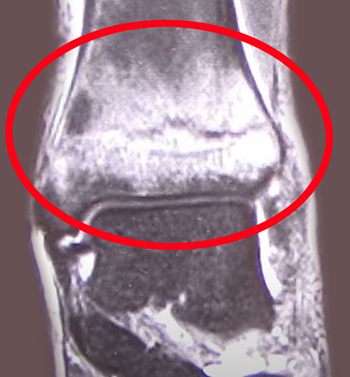

不完全骨折までいかず、骨の内出血を起こしている状態が、『骨挫傷』です。

骨挫傷は、レントゲンやCTでは骨の異常は発見できません。

MRIで骨の内部の内出血有無を調べます。